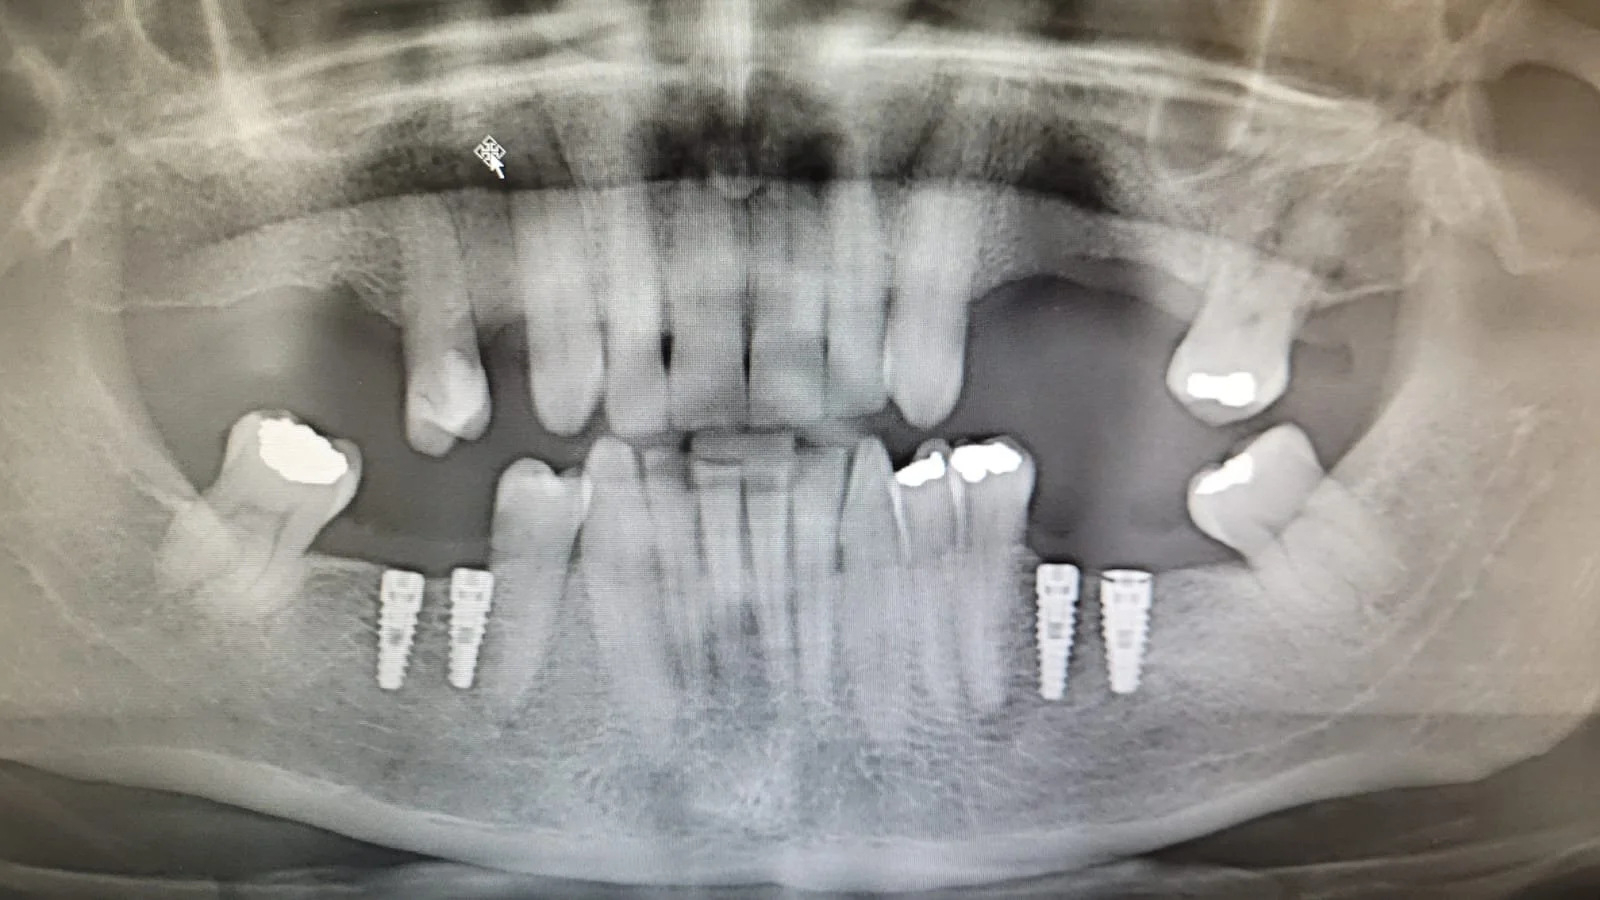

En la primera sesión realizaremos una evaluación integral de tu salud oral. Tomaremos radiografías y fotografías clínicas para analizar con detalle el estado de tus dientes y encías. También responderé tus dudas y te entregaré recomendaciones personalizadas para mantener una rutina de higiene oral efectiva.

Clínica Cipo es un centro odontológico de referencia en el sector oriente de Santiago, con más de tres décadas de experiencia entregando atención de primer nivel. Fundada y dirigida por el Dr. David Rosenberg, reconocido implantólogo a nivel nacional e internacional, la clínica se ha consolidado como un espacio donde la excelencia clínica y la calidez humana van de la mano.

Contamos con un equipo de especialistas altamente capacitados en distintas áreas de la odontología, lo que nos permite ofrecer soluciones integrales y personalizadas para cada paciente. Incorporamos tecnología de última generación en nuestros diagnósticos y tratamientos, asegurando precisión, eficiencia y resultados duraderos.